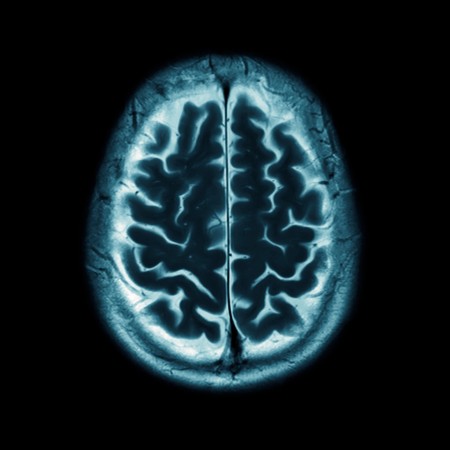

Perfusing fixatives through the cerebrovascular system is the gold standard approach in animals to prepare brain tissue for spatial biomolecular profiling, circuit tracing, and ultrastructural studies such as connectomics.

McKenzie et al. present a systematic review of four databases to consolidate the progress made so far in adopting this technique.